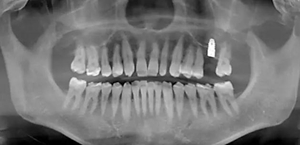

患者:男,37歲。左上后牙確實(shí)多年。既往體健,否認(rèn)麻醉和牙槽外科禁忌。

術(shù)前口內(nèi)照

術(shù)前CBCT檢查

骨高度不足,內(nèi)提升的適應(yīng)癥??梢?jiàn)竇膜致密,厚度均勻。骨高度不足,骨寬度尚可。